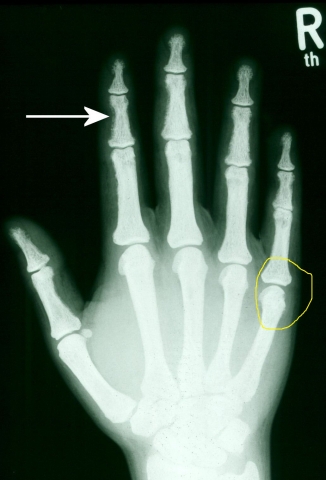

MRT Schulter links weiße FleckenWenn Ihr Schmerzen in der Schulter habt, solltet Ihr auf jeden Fall einen Arzt aufsuchen. Aber wisst Ihr auch, dass manchmal eine MRT-Aufnahme notwendig ist, um die Ursache der Probleme zu finden?

Auf dem Bild seht Ihr eine MRT-Aufnahme einer Schulter mit weißen Flecken. Diese können auf verschiedene Erkrankungen hindeuten, z.B. eine Entzündung oder Verletzung.

ZDF-Sportstudio Katrin Müller-Hohenstein: Dann macht sie Schluss www.promipool.deTrümmerbruch Am Kleinen Finger - Erfahrungsberichte (Fußball